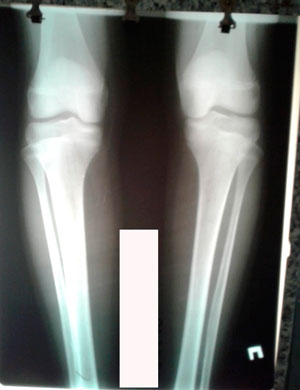

Исходник - 13 лет.

Диагноз: варусная деформация голеней + Ротация с обеих сторон.

Дата операции - 30.06.2020